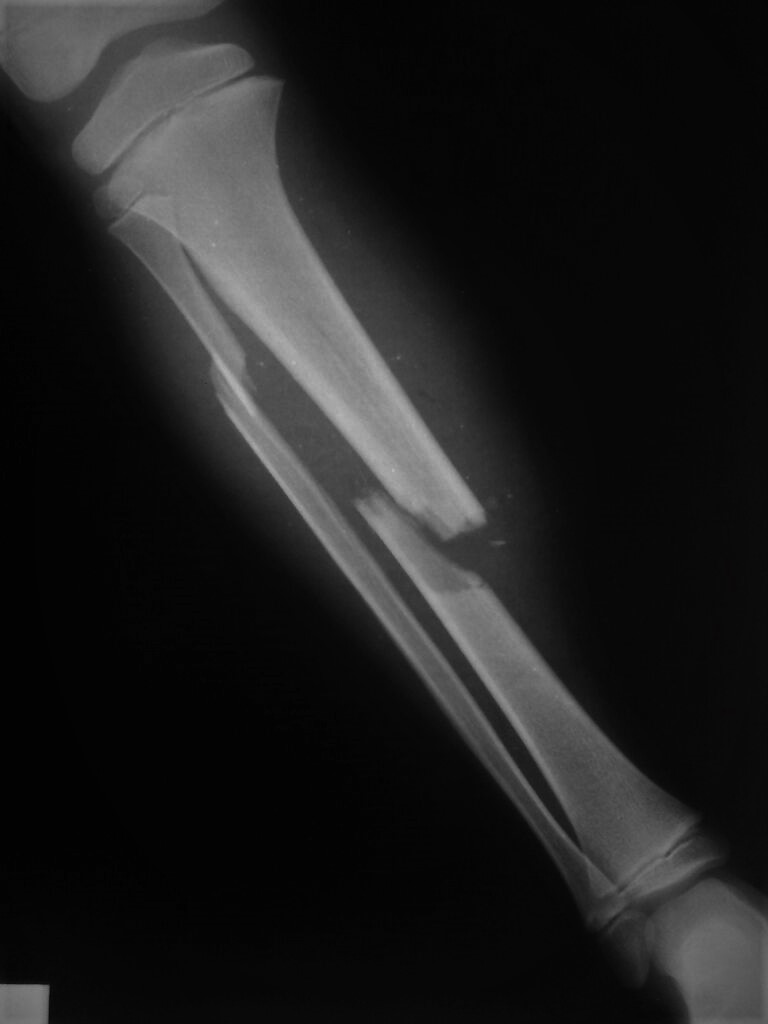

Artigo Atualização FRATURAS DA DIÁFISE DA TÍBIA EM CRIANÇAS TIBIAL DIAPHYSEAL FRACTURES IN CHILDREN Cláudio Santili , Caetano

Trauma ortopédico e Síndrome dos Maus Tratos – O que o médico precisa saber. Fraturas ocultas: quando suspeitar